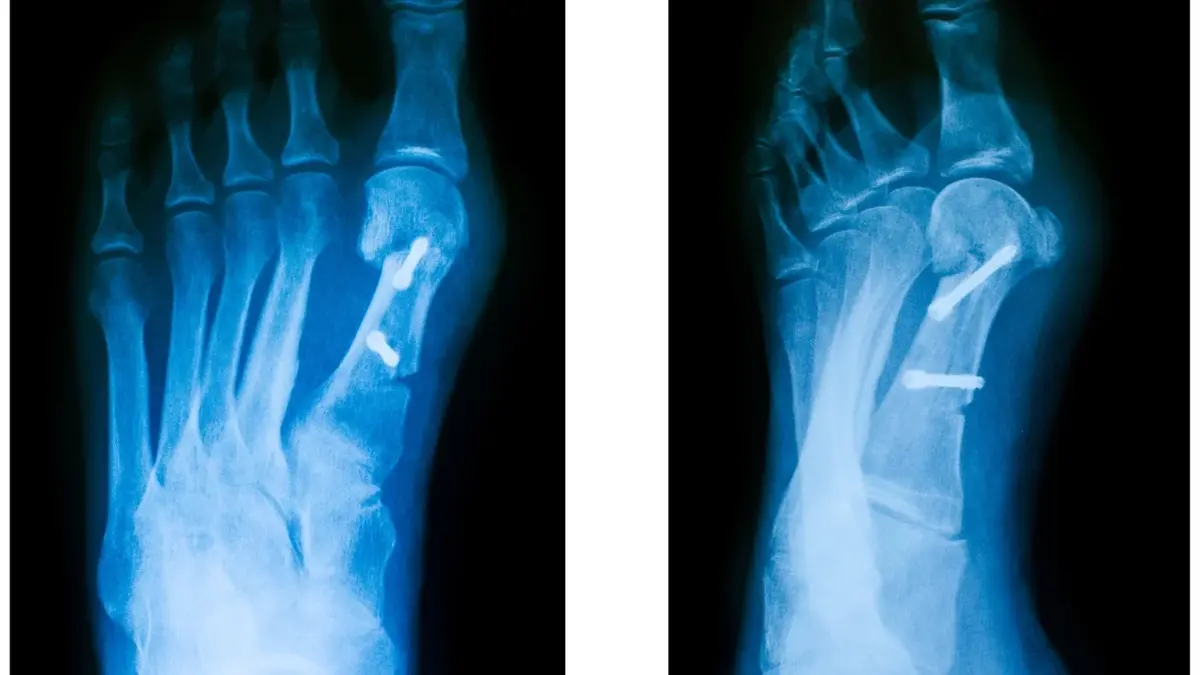

- Konsultacja z lekarzem - jeśli objawy halluksów są bardzo dokuczliwe, warto skonsultować się z lekarzem, który może zalecić dalsze leczenie, takie jak fizjoterapia lub nawet operacja.